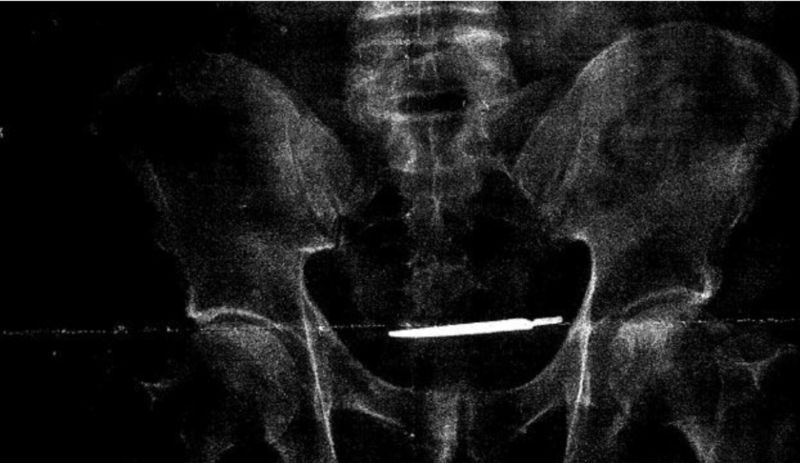

Sau khi chụp quang tuyến, người ta thấy có một con dao mổ bị bỏ quên trong người ông Turner.

Đây là con dao được dùng trong việc mổ tuyến tiền liệt (prostate) cho ông Turner bốn năm trước đây, cũng tại bệnh viện này.

Con dao mổ sau đó được lấy ra ở nơi gần bao tử và ruột của ông Turner, trong cuộc giải phẫu hồi Tháng Tư 2017.